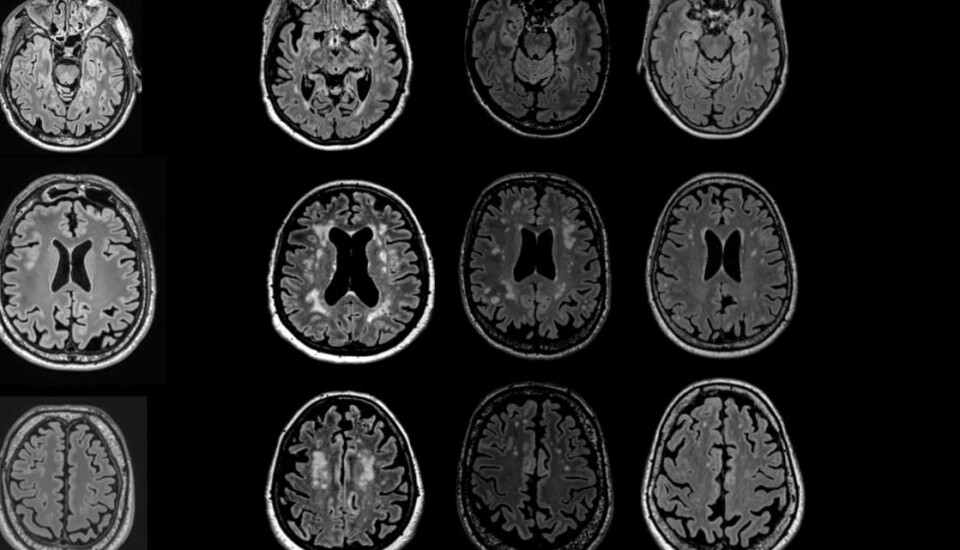

Here are MRIs of different brains with varying degrees of white spots.

It’s quite possible that you are one of those people with white spots on the brain. Healthy people aren’t spared them, but sick individuals may be more vulnerable. If you smoke, the risk increases even more.

Then you can see them. White spots on the brain. These are scars in your white matter.

Just to reassure folks a bit in closing: the white spots have varying degrees of severity.